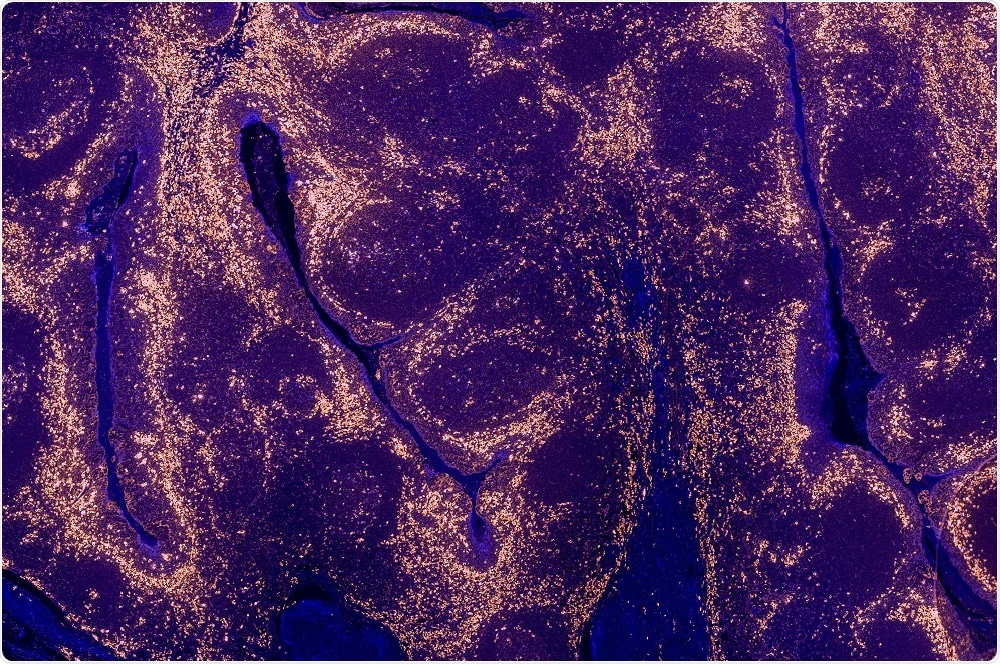

Credit: Carl Dupont/Shutterstock.com

The use of these organoids, which are tiny 3-D spheres derived from a patient’s tumor, could help guide the precision treatment of individuals with bladder cancer in the future.

As reported in the journal Cell, Shen and colleagues developed organoids from the tumor cells of 22 patients with invasive bladder cancer. The organoids appeared similar to the original tumors and exhibited many of the same molecular and genetic characteristics.